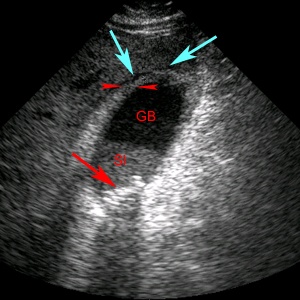

Острый холецистит на УЗИ